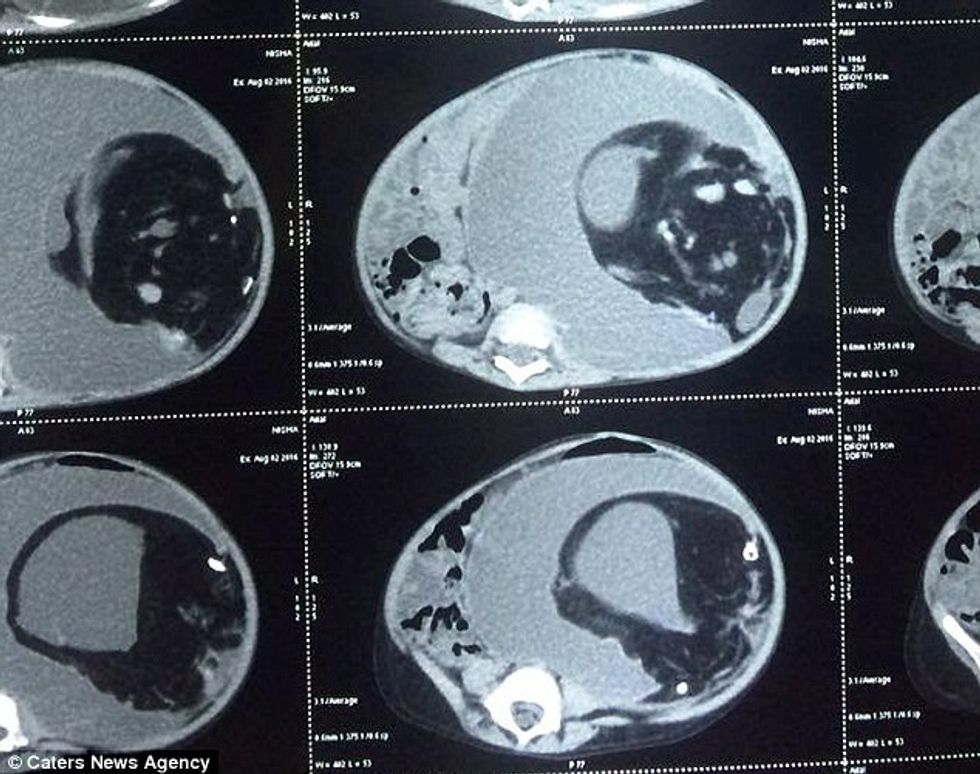

Në barkun e fryrë të vajzës së vogël, e cila nuk mund të hante apo të pinte, mjekët nxorën binjaken e saj të pa lindur.

Mjekët e një spitali në Tamil Nadu të Indisë, janë befasuar kur e kanë gjetur masën që peshonte 3.5 kilogramë, e që përmbante mish, eshtra dhe flokë, transmeton Telegrafi.

Në fakt, kjo gjendje e rrallë që quhet ‘fetus in fetu’, ndodhë kur fetusi i njëri binjak, hyn te tjetri dhe nuk lindë më kurrë. Mirëpo, në këtë rast kjo është rritur shumë dhe në mënyrë të shpejtë.

Për pasojë, vajza e quajtur Nisha nuk mund të hante asnjë ushqim, dhe ishte e uritur tërë kohës. /Telegrafi/